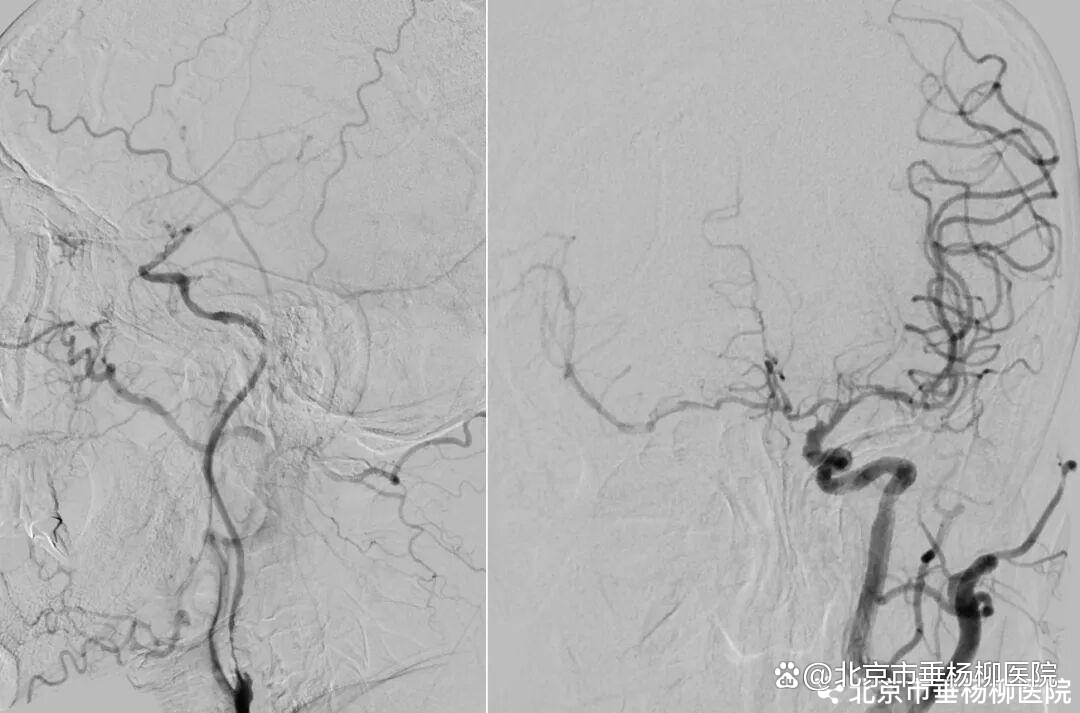

患者高先生,70岁,患有高血压病多年。2年前曾行冠状动脉搭桥术,平素规律服药。2个月前,他因左上肢突然麻木被送至清华大学垂杨柳医院急诊科就诊。头颅CT提示右侧顶叶少量蛛网膜下腔出血。后入住神经外科进一步诊治,全脑血管造影(DSA)结果显示:右侧椎动脉起始部重度狭窄约70%,左侧椎动脉颅内段闭塞;右侧椎动脉颅内段存在大小约3.5×2毫米的夹层动脉瘤;右侧颈内动脉颅外段存在重度狭窄,左侧颈内动脉通过前交通动脉代偿。

▲右侧椎动脉V4段夹层动脉瘤

▲右侧颈内动脉颅外段重度狭窄,左侧颈内动脉代偿右侧颅内